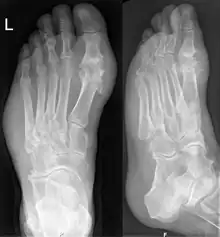

Les radiographies sont normales au début et ne servent qu'à exclure un autre diagnostic. En revanche elles servent à rechercher les conséquences osseuses ou articulaires de la goutte chronique (arthropathie goutteuse).

Le taux sanguin d'acide urique (uricémie) peut diminuer, voire se normaliser, durant la crise et un dosage normal n'exclut donc pas le diagnostic[18]. Il faut alors répéter le dosage quelques semaines plus tard. Le seuil normal d'acide urique dans le sérum est de 70 mg/L, soit 420 µmol/L. Au-delà de ces quantités, on parle d'hyperuricémie. Attention à ne pas faire un faux diagnostic de goutte chez une personne avec une simple arthrose du gros orteil (par exemple un hallux valgus) ou du genou et une hyperuricémie.